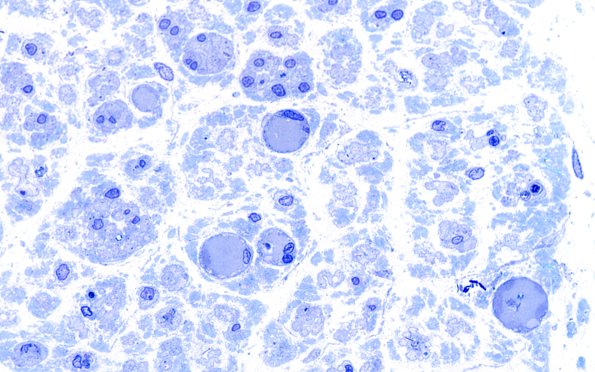

Washington University Experience | PERIPHERAL NEUROPATHY | 19 TRAUMATIC INJURIES | 16B6 Regeneration, frustration (Case 16) Plastic 100X 1

These plastic sections show the endoneurium of one of the fascicles in this biopsy, demonstrating severe loss of normal large and small myelinated axons as well as glassy large axonal spheroids (arrowheads, 16B4).